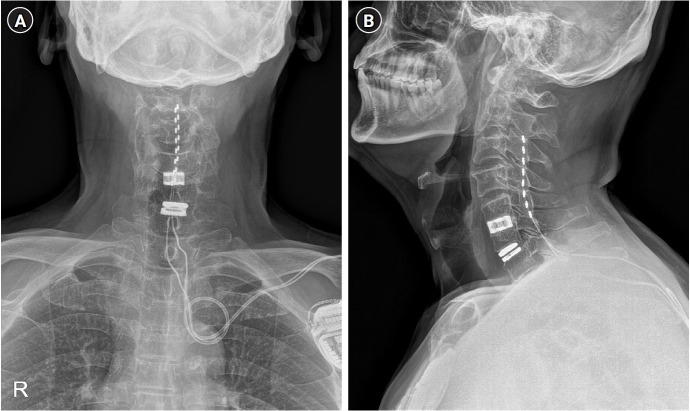

Case: A 64-year-old male patient underwent spinal cord stimulation (SCS) for severe cervical SCI. We proceeded with the ITDD system, placing the catheter tip at the C6 level. After placement of the ITDD system, the patient was monitored for regular refills of morphine sulfate in the drug delivery reservoir every 6 months. We reduced the oral morphine equivalent dose from nearly 333.8 mg/day to 133.8 mg/day.